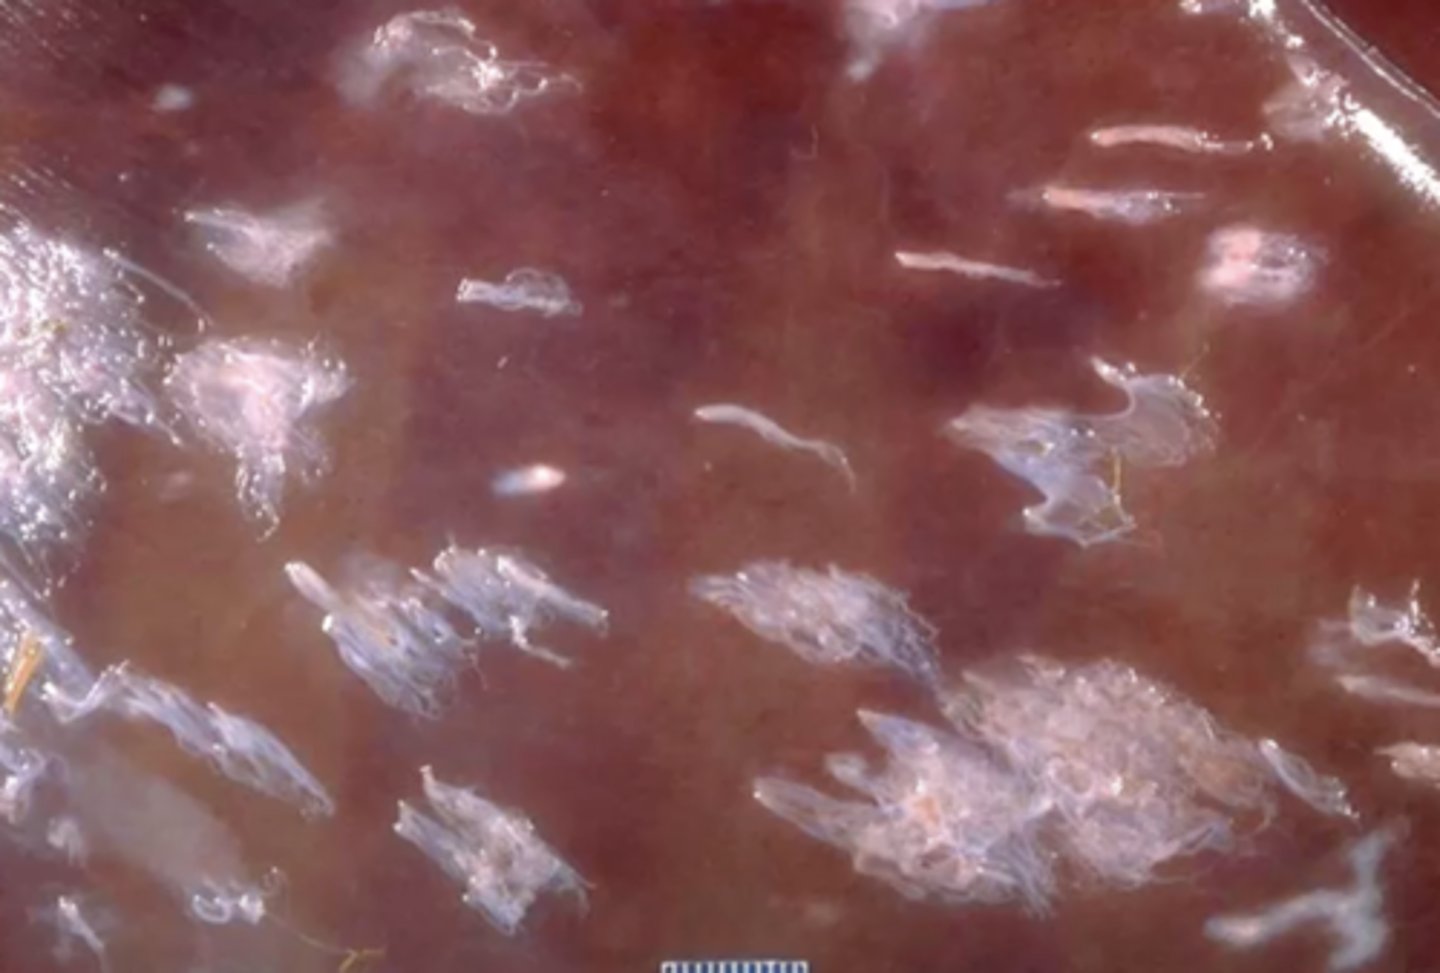

Capsular fibrosis

What is the name for the gross appearance of this liver, causing these discrete fibrous tags or plaques?